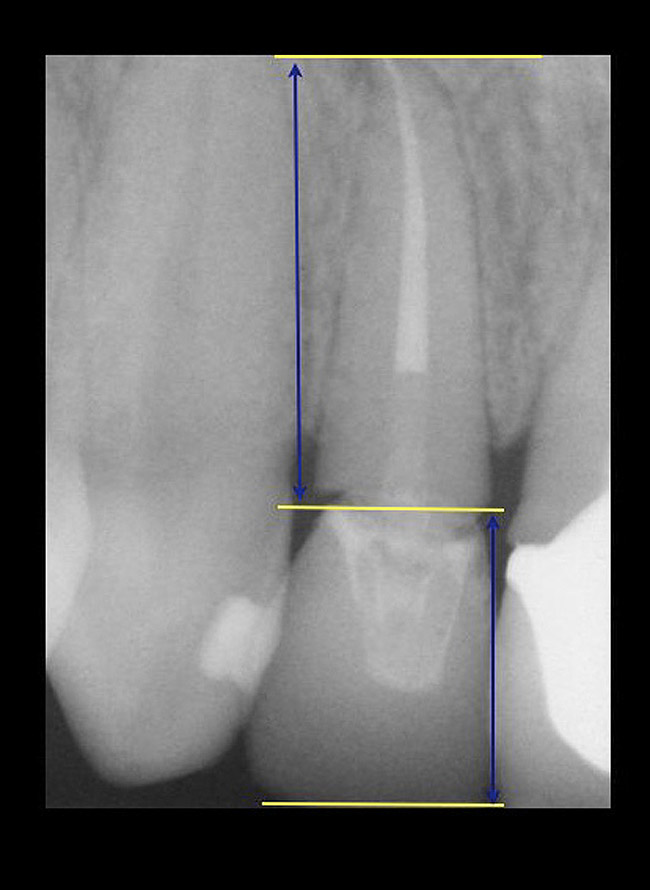

If the tooth has been endodontically treated, the remaining tooth structure relative to the post space needs to be evaluated. The Rule of Thirds is used in this situation. It states that the canal or canal space preparation should not be any wider than one third the mesiodistal root diameter after the endodontic access (Figure 3).3 Once the clinician determines whether adequate tooth structure is present, the second area to evaluate is the distance of the fracture/caries from the crest of bone. To avoid biological width impingement, the minimum distance needed from the osseous crest to the final margin placement is 2.5 mm (Figure 4). As determined in cadaver studies, this consists of approximately 1 mm of connective tissue attachment, 1 mm of junctional epithelium, and 0.5 mm of gingival sulcus.4 This measurement is meant as a guideline and not an absolute number, as it has been shown to have individual variability.5 This actual dimension for the individual patient can be predictably determined by sounding to bone on the adjacent teeth to more closely determine the individual’s biologic width.6

The clinical guideline of 4 mm—consisting of 1.5 mm of tooth structure and 2.5 mm biologic width1,3—is, therefore, the minimum limit for tooth structure above the alveolar bone (Figure 5). If this parameter cannot be met, there are two options for obtaining this threshold. One option is surgical crown lengthening,7,8 and the other is forced orthodontic eruption.9 The choice between each option should be made based on the effect each procedure will have on the esthetics of the case, the crown-to-root ratio, and whether osseous surgery will create a furcation involvement on the adjacent teeth (Figure 6). Esthetic considerations will be addressed later. In terms of crown-to-root ratio, there are two guidelines that exist for determining the minimum ratio (Figure 7). One is the classical 1:1 presented by Penny.10 The second, for maxillary anterior teeth, is 12 mm to 13 mm of tooth with 8 mm to 9 mm of root in bone and 4 mm coronal to the bone, as presented by Spear.1 If all of these criteria for tooth structure are met, then the tooth should be considered an acceptable candidate for retention and restoration. Also, if insufficient tooth structure exists, the required tooth structure can be obtained via forced orthodontic eruption or periodontal surgery provided that the esthetics and periodontal function of the tooth in question and the adjacent dentition are not compromised.

Figure 4  CLINICAL GUIDELINES  The minimum distance needed is 2.5 mm from the osseous crest to the final margin placement to avoid biologic-width impingement. This measurement is meant as a guideline and not an absolute number, as it has been shown to have individual variability. This gives a clinical guideline of 4 mm consisting of 1.5 mm of tooth structure and 2.5 mm biologic width.

Figure 4

Figure 5  CLINICAL GUIDELINES  The minimum distance needed is 2.5 mm from the osseous crest to the final margin placement to avoid biologic-width impingement. This measurement is meant as a guideline and not an absolute number, as it has been shown to have individual variability. This gives a clinical guideline of 4 mm consisting of 1.5 mm of tooth structure and 2.5 mm biologic width.

Figure 5

Figure 7  CLINICAL GUIDELINES  There are two methods for decisions based on crown-to-root ratio. One is the classical 1:1. The second, for maxillary anterior teeth, is 12 mm to 13 mm of tooth with 8 mm to 9 mm of root in bone and 4 mm coronal to the bone.

Figure 7